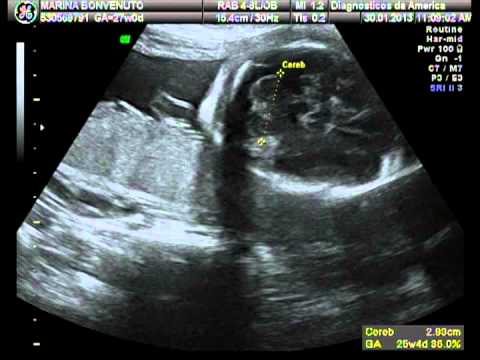

Esse é o meu primeiro vídeo..Isso porque os cabeçudos dos meus pais foram na primeira vez justo num lugar onde a máquina estava quebrada para gravação do CD. Mas dessa vez eles foram mais que preparados com 4 tipos diferentes de CD regravável....Como disse meu pai: Para não dar azar de novo. E assim vocês vão ver como eu já estava lindo e esperto com 25 semanas. Não posso deixar de contar é claro (se não meu pai me mata) que nesse dia o doutor era todo engraçadinho e ficou falando que eu ia ser de um time muito feio....Eu não sabia direito, agora minha mãe já me ensinou que não pode fazer isso, mas eu fiquei irritado e mostrei um dos dedos da minha mão pra ele. Na hora eu ouvi um monte de risada, mas acho q deve ter sido de outra coisa então né?

Tirando isso deu pra eles verem que eu já tinha a boquinha do meu pai, um pé enorme e já estava chupando o dedo.